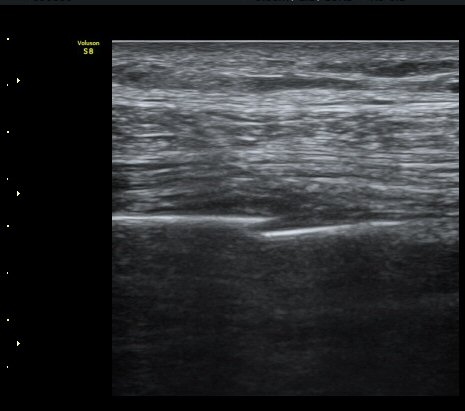

¹Ì¼¼ÇÏ°Ô °¥ºñ»À ÇÇÁú°ñ ¿¬°á¼º ¼Ò½Ç°ú ¿¬ºÎÁ¶Á÷ ºÎÁ¾ÀÌ °üÂûµÊ (loss of cortical continuity and soft tissue swelling of rib) »çÁø 1

°¥ºñ»À ÇÇÁú°ñ ¿¬°á¼º ¼Ò½Ç°ú ¾à°£ÀÇ ÀüÀ§, ¿¬ºÎÁ¶Á÷ ºÎÁ¾ÀÌ °üÂûµÊ (loss of cortical continuity and soft tissue swelling of rib)  »çÁø 2

°¥ºñ»À °ñÀý ÈÄ Å« ÀüÀ§°¡ °üÂûµÊ(fracture with displacement) »çÁø 3

±¤¹è±Ù ½ÉºÎ¿¡ °¥ºñ»À»çÀ̱ÙÀÌ °üÂûµÇ°í °¥ºñ»À»çÀٰ̱ú Æó»çÀÌ¿¡ ¼ö¾×Àú·ù°¡

°üÂûµÊ(intercostal muscle deep to latissimus dorsi, fluid accumulation between intercostal muscle and lung)   »çÁø 4

°¥ºñ»À »çÀÌ¿¡ °¥ºñ»À»çÀ̱ÙÀÌ °üÂûµÇ°í °¥ºñ»À»çÀٰ̱ú Æó»çÀÌ¿¡ ¼ö¾×Àú·ù°¡

°üÂûµÊ (intercostal muscle between ribs,  fluid accumulation between intercostal muscle and lung) »çÁø 5    µ¿¿µ»ó

°ñ°Ý°èÃÊÀ½ÆÄ°Ë»ç´Â °¥ºñ»ÀÀÇ ¹Ì¼¼°ñÀýÀÇ Áø´Ü »Ó ¾Æ´Ï¶ó, °ñÀýµÈ °¥ºñ»ÀÀÇ ÀüÀ§ Á¤µµ,

°ñÀý¿¡ ÀÇÇÑ Ç÷ÈäÀ̳ª ±âÈäÀÇ Áø´Ü¿¡ ÀÌ¿ëÇÒ ¼ö ÀÖ´Ù.